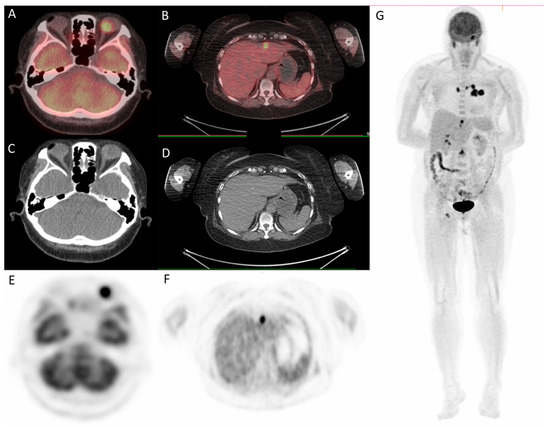

Since the patient had a family history of lung cancer, whole-body positron emission tomography/computed tomography (PET/CT) was suggested; the results showed focal uptake in the left eye with a standardized uptake value (SUV) of 10.8, left upper lung (SUV: 11.5), mediastinum (SUV: 14.8), liver (SUV: 9.6), and bone (SUV: 10) (Figure 5 and Figure 6).

Figure 6.

18F-fludeoxyglucose positron emission tomography/computed tomography (18F-FDG PET/CT) for whole-body evaluation. (A,B) axial fused PET/CT showing focal uptake of left eye and liver, respectively; (C,D) axial CT; (E–G) PET. PET/CT.

In the last decade, conventional imaging modalities, such as plain radiography, ultrasound, CT, and magnetic resonance imaging, have been widely used to provide clear structural images of the tumor [16]. PET, which uses short-lived radioisotopes, such as fluorine-18 to label glucose, can detect malignancy and be used for staging, restaging, or monitoring treatment responses [17]. PET combined with CT provides simultaneously high sensitivity of tracer distribution and high precision of localization, facilitating the detection of tumor sites in patients with choroid metastasis. In the present case, PET/CT scan was utilized early for detection of tumor sites, and it highlighted multiple uptakes in the left eye, left upper lung, mediastinum, liver, and bone. In addition to providing useful clues to the possible primary tumor sites, it was fast and efficient.